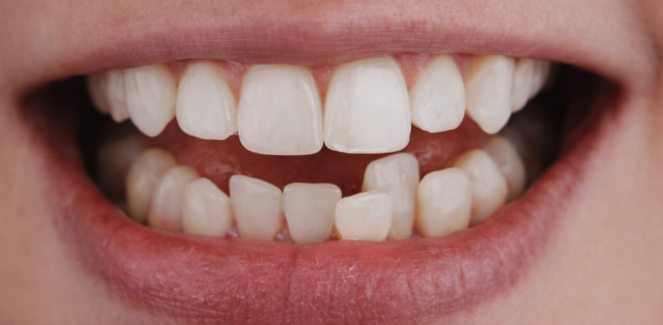

- ✔️ Cosmetic Dental Treatments

- ✔️ Clear Aligners